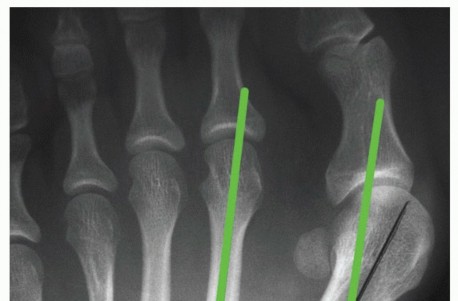

DEFINITION Hallux valgus is a deformity of the forefoot characterized by progressive lateral subluxation of t…

SURGICAL MANAGEMENT The primary indication for a proximal closing wedge osteotomy is a symptomatic hallux val…